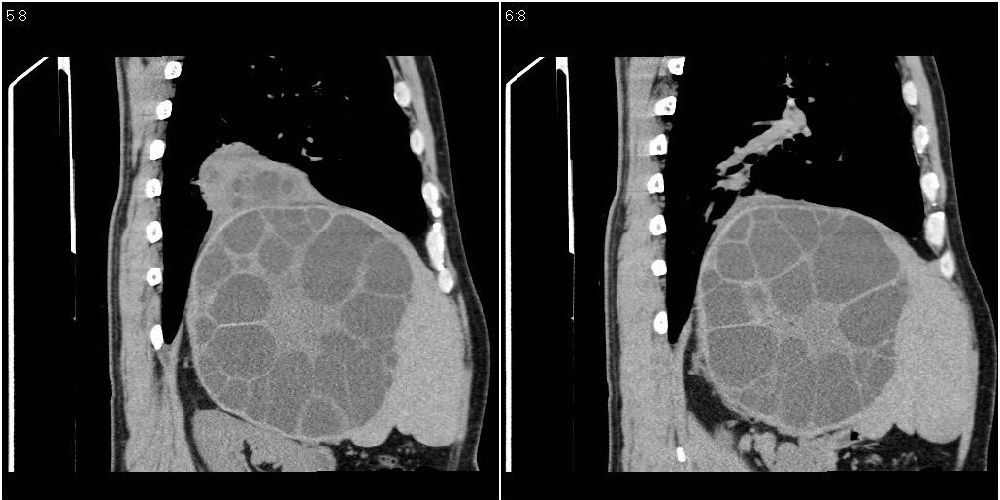

该患者70岁男性,手术后10年,现复查。2008年6月份本人曾经发过一极其类似的病例,只是部位略有差异。

肝脏多房性包虫囊肿

水上浮莲征,肝包虫囊肿。

大囊套小囊!肝脏多房性包虫囊肿

肝脏及右侧胸腔包虫病。